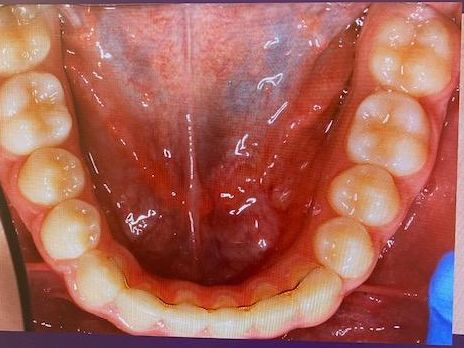

Quad Helix regulering på tenner i overkjeve

Annen apparatur

Ved behov benyttes også annen reguleringsapparatur, blant annet Quad Helix og tommelfingersperre. Valg av apparatur tilpasses bitt og tannstilling.